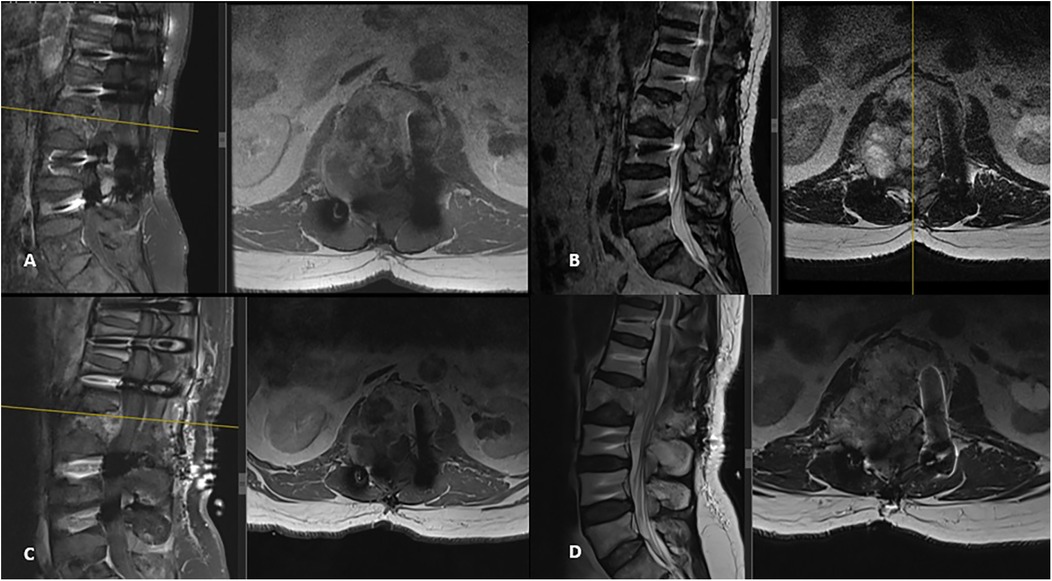

A 67-year-old male patient presented to our outpatient clinic with a complaint of low back pain that had begun 6 months prior. During the past month, the pain had started to radiate into his left leg. Neurological examination revealed muscle strength of 4/5 in the left tibialis anterior and extensor hallucis longus, along with localized tenderness upon palpation over the L2 vertebra. Magnetic resonance imaging (MRI) revealed a mass involving the right pedicle and body of the L2 vertebra. There was a 50% reduction in vertebral body height at this level, with partial tumor extension into the spinal canal and compression of the thecal sac from the right side (Figures 1A,B). The lesion appeared hypointense on T1-weighted images and hyperintense on T2-weighted images and exhibited diffuse contrast enhancement. An FDG-PET/CT was also performed, which demonstrated increased uptake at the L2 vertebra (SUVmax, 12.5), suggestive of metastasis. No intracranial lesions exhibited increased uptake or produced mass effect on the FDG-PET/CT (Figure 2). Based on these findings, the lesion was initially considered a potential metastatic tumor, and surgical intervention was scheduled. Surgery was performed via a posterior approach. A total laminectomy at L1 and right-sided hemipartial laminectomy at L2 were conducted to achieve subtotal decompression and tumor removal. Posterior stabilization from T11 to L4 was achieved using bilateral pedicle screws, with unilateral placement at the L2 level on the left side (Figure 1C). The lesion was entirely extradural. Histopathological examination revealed nodular tumor tissue within a rich vascular background, characterized by focal, prominent epithelial proliferation. The tumor cells were predominantly clear, partially physaliphorous, and partially eosinophilic with abundant cytoplasm, showing low-grade atypia. While mucin was present in small areas and there were single-layered cell patterns resembling adenoid structures, well-formed glandular architecture was not identified. Immunohistochemically, the tumor was strongly positive for vimentin, CDX2, TTF-1 (in 25% of cells), epithelial membrane antigen (EMA), and Pan-CK (5/6/8/18). It was negative for S-100, CK-20, CK-7, CK-5/6, CD10, and renal cell carcinoma (RCC). Brachyury staining was not performed. Due to the absence of S-100 positivity, a diagnosis of chordoma was ruled out. Although CDX2 positivity indicated intestinal differentiation, the lack of CK7 and CK20 expression, which are typically seen in gastrointestinal tumors, argued against that origin. Possible primary sources considered included adrenal, hepatic, and prostatic carcinomas. A definitive diagnosis could not be established, and the lesion was interpreted as a metastasis of clear cell carcinoma from an unknown primary. The postoperative course was uneventful, his symptoms were resolved, and the postoperative neurological examination of the patient was unremarkable. Stereotactic radiosurgery (TruBeam) was administered, delivering a total dose of 30 cGy in 10 fractions to the tumor site.

Figure 1. Preoperative MRI: (A) T1-weighted sagittal and axial MRI with contrast, (B) T2-weighted sagittal and axial MRI revealed a mass lesion involving the right pedicle and body of the L2 vertebra. There was approximately 50% height loss of the vertebral body at that level, with partial tumor extension into the spinal canal causing compression of the thecal sac from the right side. The lesion demonstrated diffuse contrast enhancement and appeared hyperintense on T2-weighted images. (C) Postoperative T2-weighted sagittal and axial images showed a total laminectomy at L1 and right hemipartial laminectomy at L2, subtotal tumor removal, and decompression. Note the use of unilateral (left) pedicle screws at the L2 level.

Three years after the initial operation, the patient presented with complaints of newly developed right-sided sciatica. Neurological examination at this time was unremarkable. A follow-up spinal MRI revealed the progression of the remnant tumor in the same region (Figures 3A,B). The patient underwent a second surgical procedure, during which the tumor was again removed subtotally (Figures 3C,D). As in the previous operation, the tumor was found to be purely extradural. This time, histopathological and immunohistochemical analysis of the specimen confirmed the diagnosis of chordoma. The tumor was predominantly composed of cells with clear or multivacuolated cytoplasm, occasionally forming chordoid and trabecular arrangements within a myxoid stroma. Immunohistochemically, the tumor cells were positive for cytokeratin (CK) AE1/AE3 and negative for S-100, RCC, CK14, CK7, CK20, and PAX8. The MIB-1 labeling index was 10%. Tumor cells showed diffuse positive staining for brachyury, a specific marker for tumors of notochordal origin. The postoperative course was again uneventful, the patients’ symptoms were relieved, and there were no neurological deficits after the surgery. Following the confirmed diagnosis of chordoma, proton beam therapy was administered with a total dose of 66 Gy delivered in 33 fractions. The spinal lesion remained stable over the next 3 years, during which the patient continued to be monitored regularly in the outpatient clinic.

Figure 3. New spinal MRI performed 3 years after the initial surgery revealed a recurrent tumor with progression in the same region. It appeared hypointense on T1-weighted images (A) and hyperintense on T2-weighted sagittal and axial images (B), showing diffuse contrast enhancement, spinal canal extension, and dural sac compression. Postoperative T1-weighted (C) and T2-weighted (D) MRI images demonstrate subtotal tumor removal and adequate decompression.